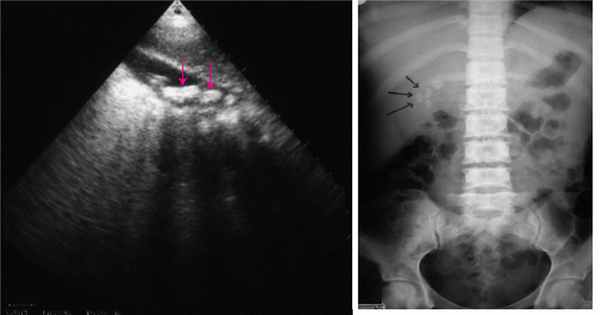

Рис. 1. Эхограмма тромбоза воротной вены. а - В-режим. Неоднородное образование повышенной эхоген-ности с неровными, нечеткими контурами в просвете воротной вены (стрелки). б - режим ЦДК. Полное отсутствие допплеровских сигналов внутри просвета сосуда; допплеровский сигнал определяется в сети мелких коллатералей.

При ультразвуковом исследовании (УЗИ) в серошкальном режиме в просвете воротной вены можно выявить неоднородное образование повышенной или смешанной эхоген-ности с неровными, нечеткими контурами, препятствующее кровотоку, размеры которого могут быть различными - от 0,5 см до полной окклюзии воротной вены и/или ее ветвей (рис. 1, а). Эхогенность тромба чаще является более высокой, чем окружающей его крови. Однако на ранних стадиях формирования эхогенность может отличаться настолько незначительно, что визуализация тромба чрезвычайно сложна. Могут определяться увеличение диаметра сосуда с нечеткостью контуров, увеличение печени и снижение ее эхогенности, увеличение селезен-

При цветовом допплеровском картировании (ЦДК) отмечают полное или частичное отсутствие допплеровских сигналов внутри просвета сосуда. При частичном тромбозе сигнал определяется пристеночно вокруг тромба, частично окклюзирующе-го вену, либо в сети узких коллатералей (рис. 1, б). При частичном тромбозе определяется допплеровский сигнал с признаками турбулентности на фоне повышенной скорости кровотока. При опухолевом тромбозе кровоток может быть пульсирующим либо непрерывным. Визуализируются мелкие или крупные коллатерали. При кавернозной трансформации воротной вены в режиме ЦДК в коллатералях определяется сглаженная допплеровская кривая со средней скоростью кровотока менее 8 см/с. Возможны кавернозные мальформации вены, спонтанные порто-портальные, портока-вальные и спленоренальные шунты.